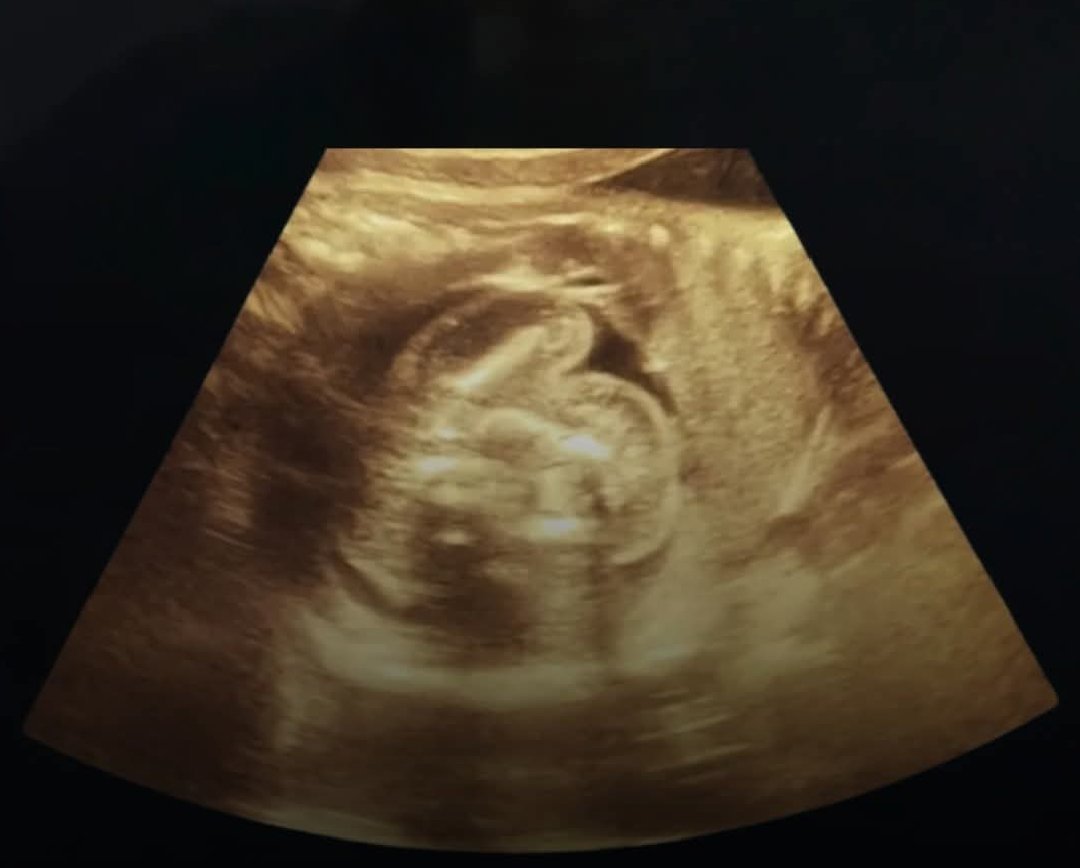

बुलंदशहर। उत्तर प्रदेश के बुलंदशहर जिले में एक ऐसा चौंकाने वाला मामला सामने आया है जिसने आम लोगों के साथ-साथ डॉक्टर्स को भी हैरान कर दिया है। यहां एक 30 वर्षीय महिला को पिछले दो महीने से पेट में लगातार दर्द और उल्टी की शिकायत थी। जब स्थानीय स्तर पर इलाज कराने के बाद भी उसे कोई राहत नहीं मिली, तो उसे एमआरआई जांच के लिए एक निजी सेंटर भेजा गया।जांच रिपोर्ट देखकर डॉक्टरों के होश उड़ गए। रिपोर्ट में महिला की प्रेग्नेंसी की पुष्टि तो हुई, लेकिन सबसे हैरानी की बात यह थी कि उसका गर्भाशय यानी यूट्रस पूरी तरह खाली था। दरअसल, महिला का 12 हफ्ते का भ्रूण उसके गर्भाशय में नहीं, बल्कि लीवर के दाहिनी ओर पल रहा था। और इतना ही नहीं, भ्रूण में स्पष्ट रूप से धड़कन भी मौजूद थी, यानी वह पूरी तरह जीवित था।इस मामले की पुष्टि करने वाले वरिष्ठ रेडियोलॉजिस्ट डॉ. के.के. गुप्ता ने बताया कि वे अपने पूरे करियर में पहली बार ऐसा मामला देख रहे हैं। उन्होंने कहा, “यह एक अत्यंत दुर्लभ मामला है। अब तक पूरी दुनिया में ऐसे केवल 18 केस ही रिपोर्ट हुए हैं, और भारत में यह संभवतः पहला मामला हो सकता है।”डॉक्टरों के मुताबिक, यह स्थिति “एबडॉमिनल प्रेग्नेंसी” यानी पेट के भीतर अन्य अंग में भ्रूण के विकसित होने का मामला है, जो सामान्य गर्भावस्था से बिल्कुल अलग और जीवन के लिए खतरनाक हो सकता है। फिलहाल महिला की स्थिति पर निगरानी रखी जा रही है और विशेषज्ञों की टीम आगे की चिकित्सा प्रक्रिया पर विचार कर रही है। यह मामला मेडिकल साइंस के लिए एक गंभीर अध्ययन का विषय बन चुका है और डॉक्टरों ने इसे लेकर विस्तृत रिपोर्ट तैयार करनी शुरू कर दी है।

लीवर में पल रहा था भ्रूण! बुलंदशहर में सामने आया चौंकाने वाला मामला, डॉक्टर्स भी रह गए हैरान